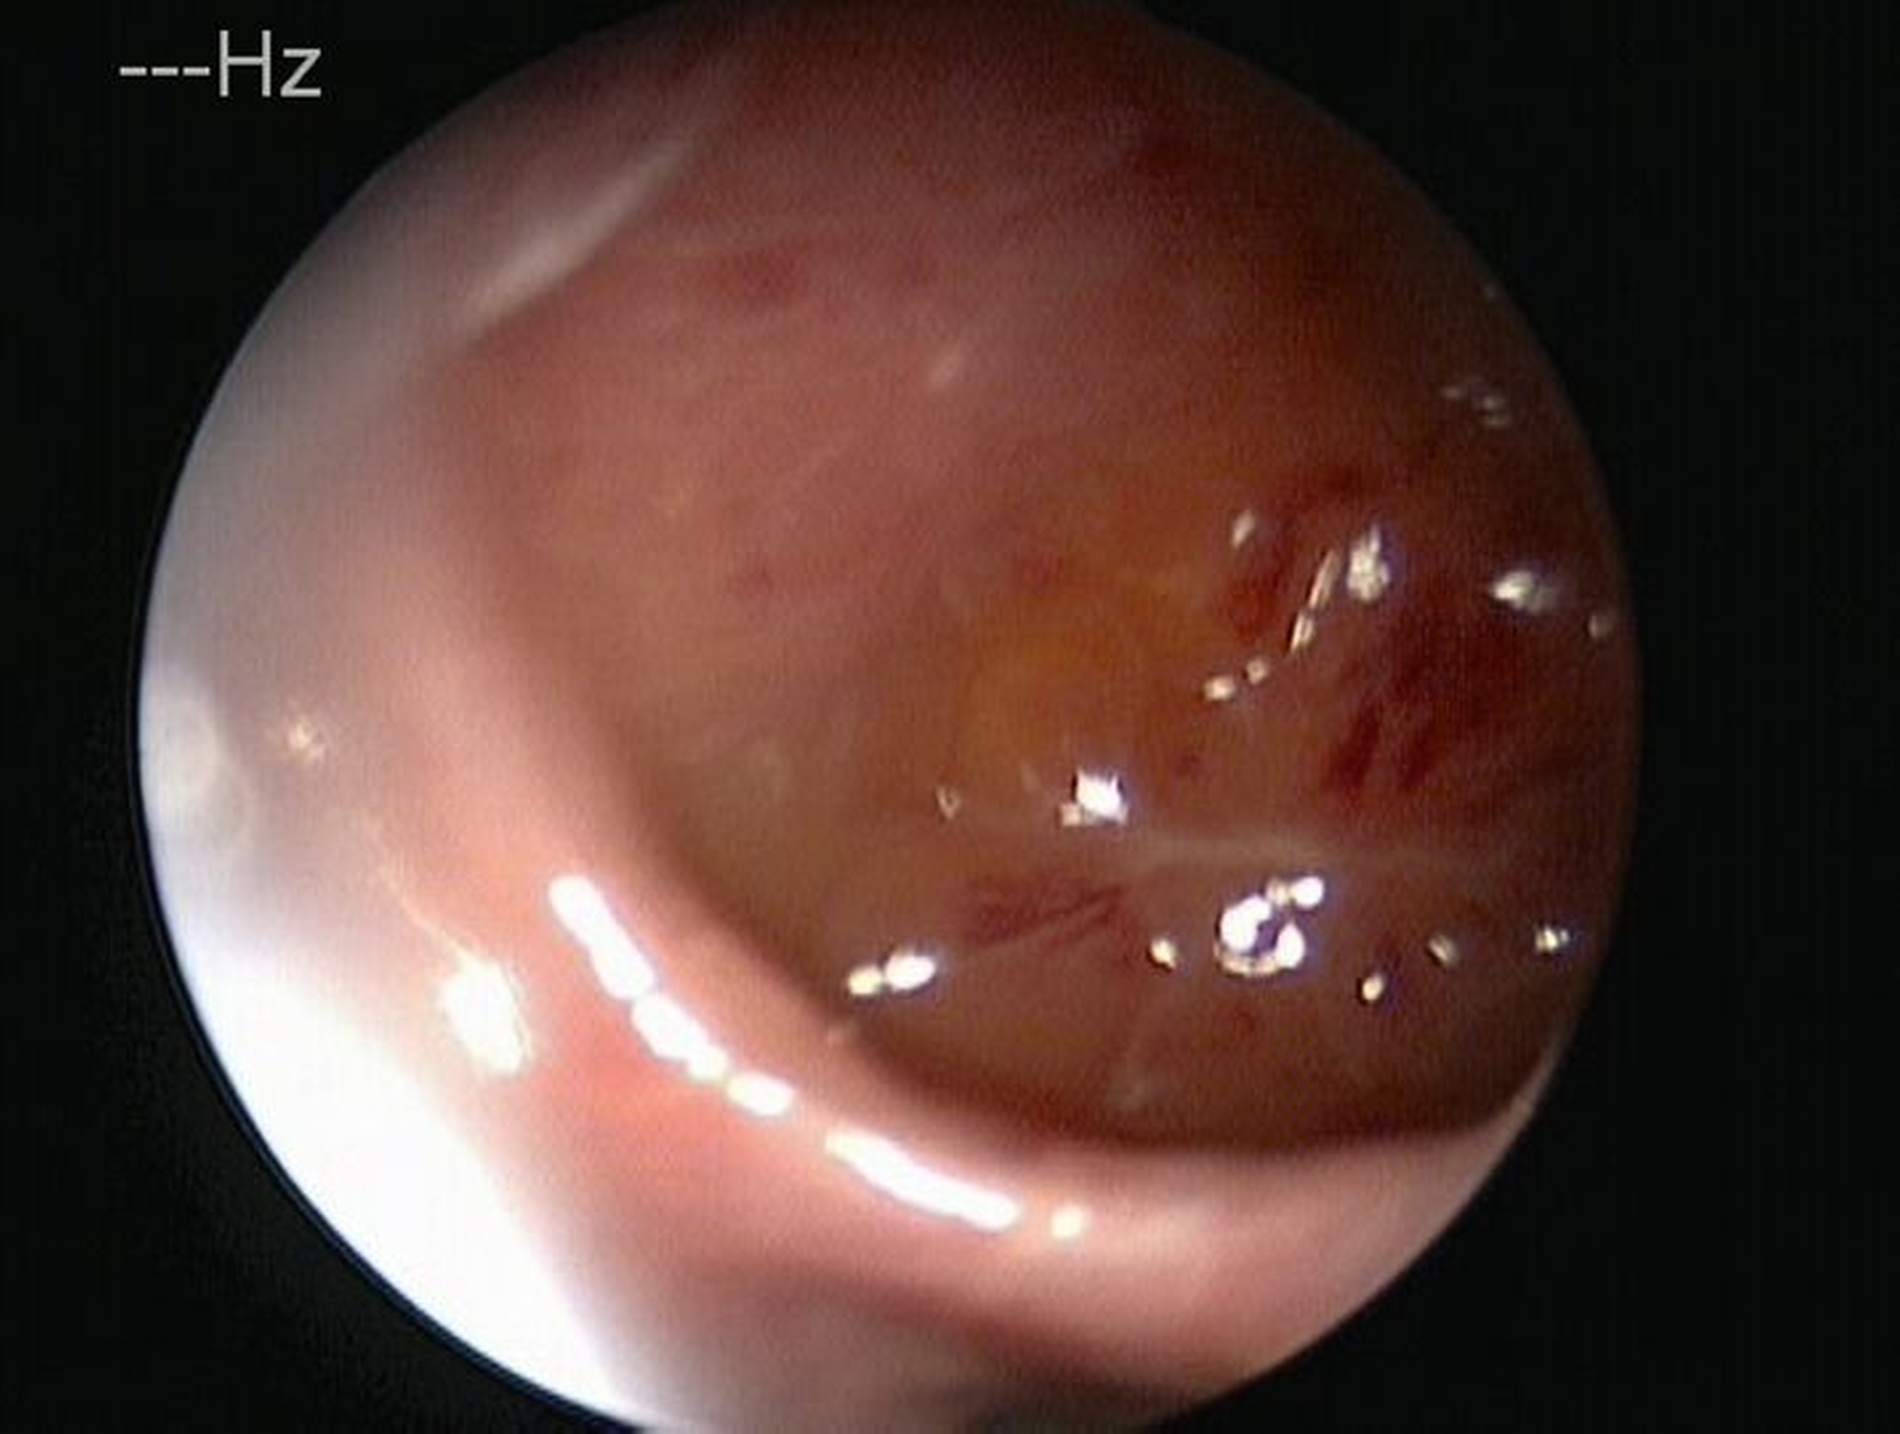

Im weiteren Verlauf wurde die Kieferhöhle durch die Easy-flow-Drainage mehrmals gespült, bis sich klares Sekret über die Nase entleerte. Eine endoskopische Untersuchung der Nase zeigte keine Anzeichen für Pilzreste (Abbildung 4). Unter diesen Umständen konnte der plastische Verschluss der Mund-Antrum-Fistel durch eine Rehrmann-Plastik erfolgen. Die weiteren Kontrollen zeigten einen regelhaften Verlauf der Wundheilung, so dass der Patientin empfohlen werden konnte, eine prothetische Versorgung im zweiten Quadranten durchführen zu lassen.